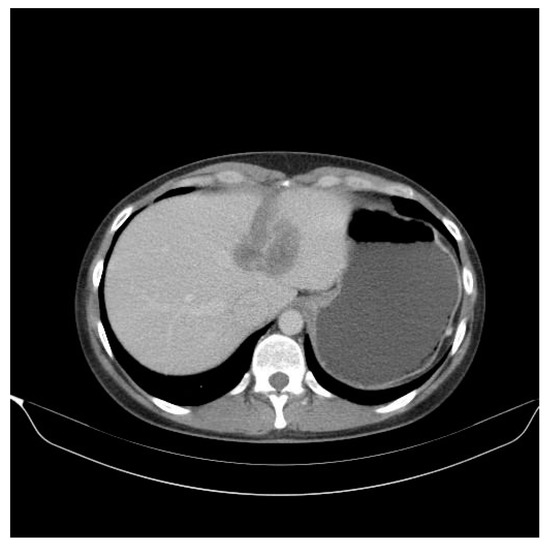

2. Case Presentation